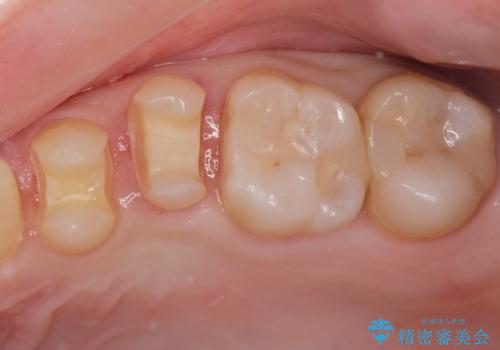

- 矯正前の患者様です。検査をしたところ虫歯が見られたので拡大鏡下で虫歯を取り除き

e-maxインレーで治療を行いました。

虫歯が多数ありましたのでまずは2本虫歯治療を行いました。